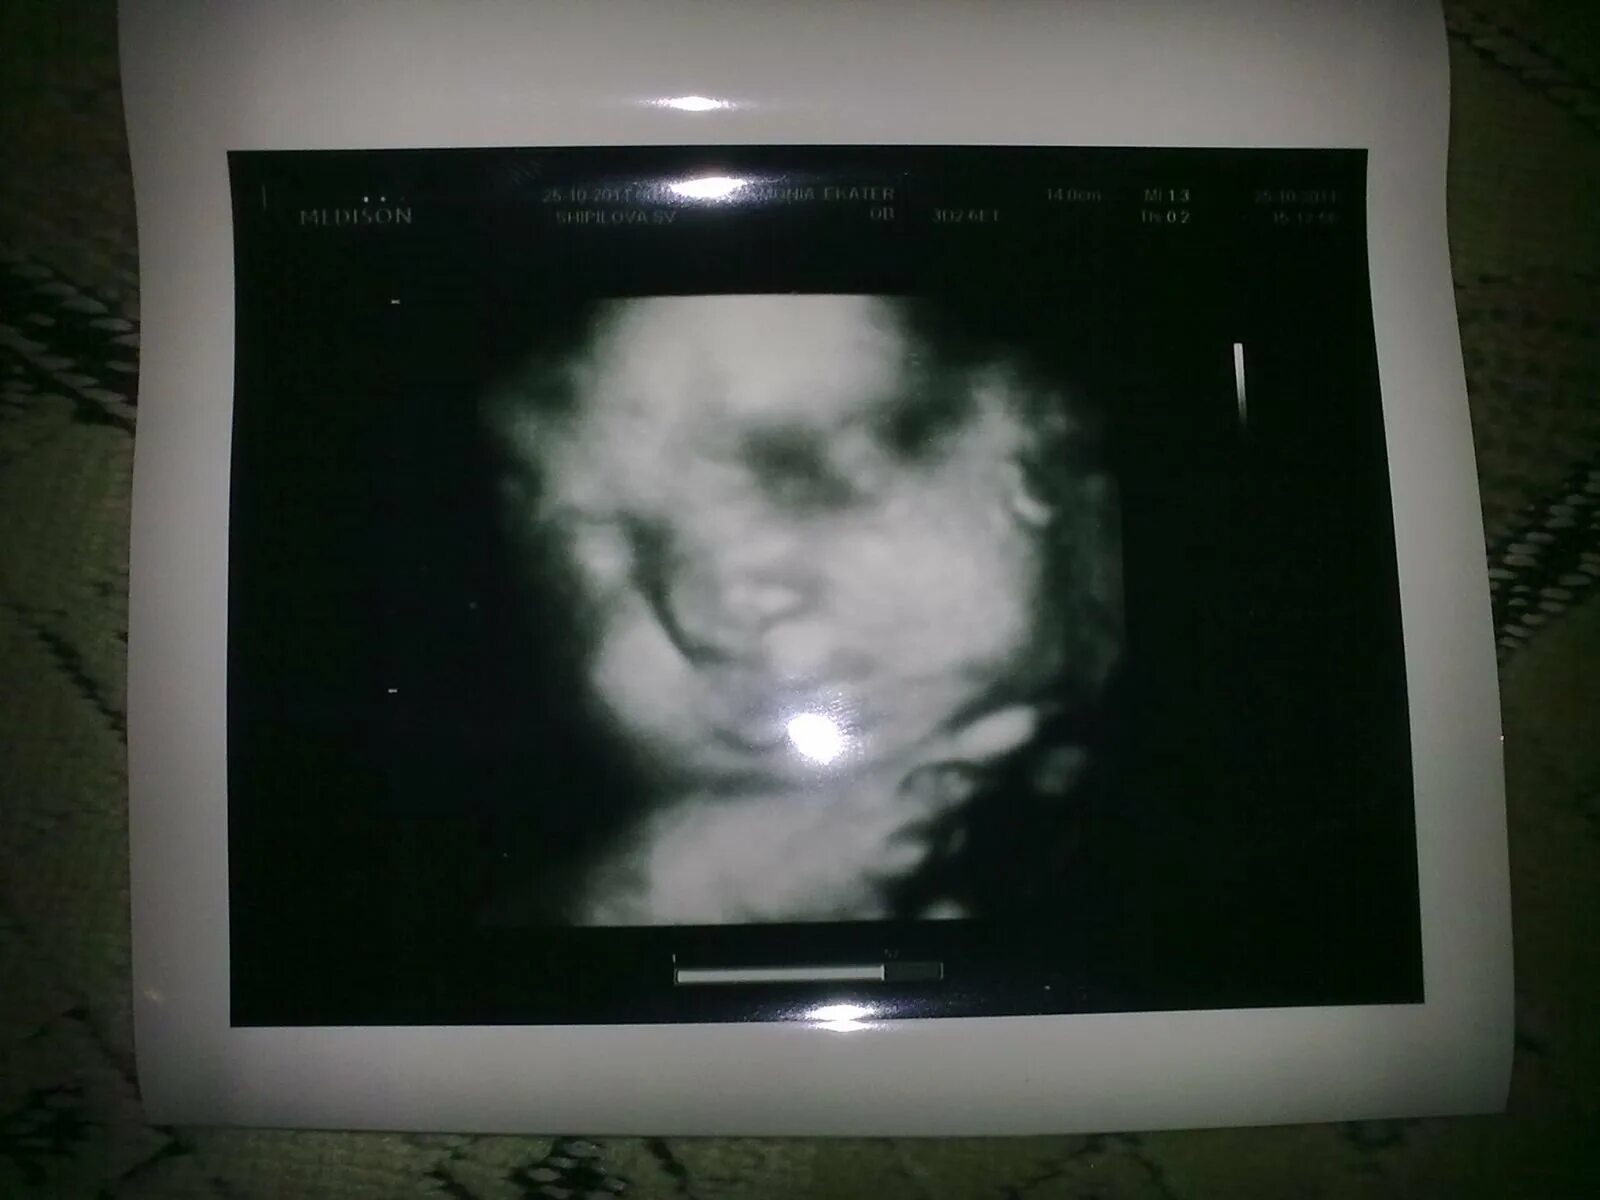

Узи 6 месяцев